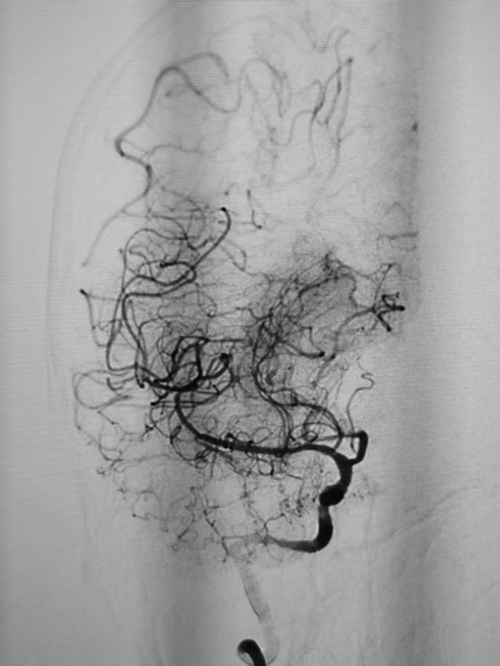

近日,70岁的宋大爷在解放军总医院神经外科医学部派驻第四医学中心神经外科完成全脑血管检查,造影结果显示其大脑中动脉、前动脉远端分支显影清晰,形态及血流均正常,无任何后遗症残留。而谁能想到,这位老人曾在两年前因急性大脑中动脉主干闭塞命悬一线,是神经外科李首春副主任医师团队以“与时间赛跑”的速度和精湛医术,为他抢回了生命与健康。

时间就是生命,提高一秒就多一分胜算。15分钟后,手术团队一切准备就绪,将病人接到手术室,他们立即给予宋大爷全脑血管造影+血管闭塞开通术。经过抽吸和支架辅助取栓,医护团队取出了大约10毫米×1毫米的血性斑块,闭塞血管顺利开通,远端血管恢复显影。术中进一步探查发现,宋大爷大脑中动脉主干存在严重狭窄,李首春副主任医师随即实施球囊扩张+血管内支架植入成形术,彻底改善血管狭窄问题。从术前准备到手术结束,整个过程仅用时1小时。术后3天,宋大爷意识清晰,语言功能恢复流利,右侧手脚活动自如;术后第4天,他已能独立步行,顺利康复出院。